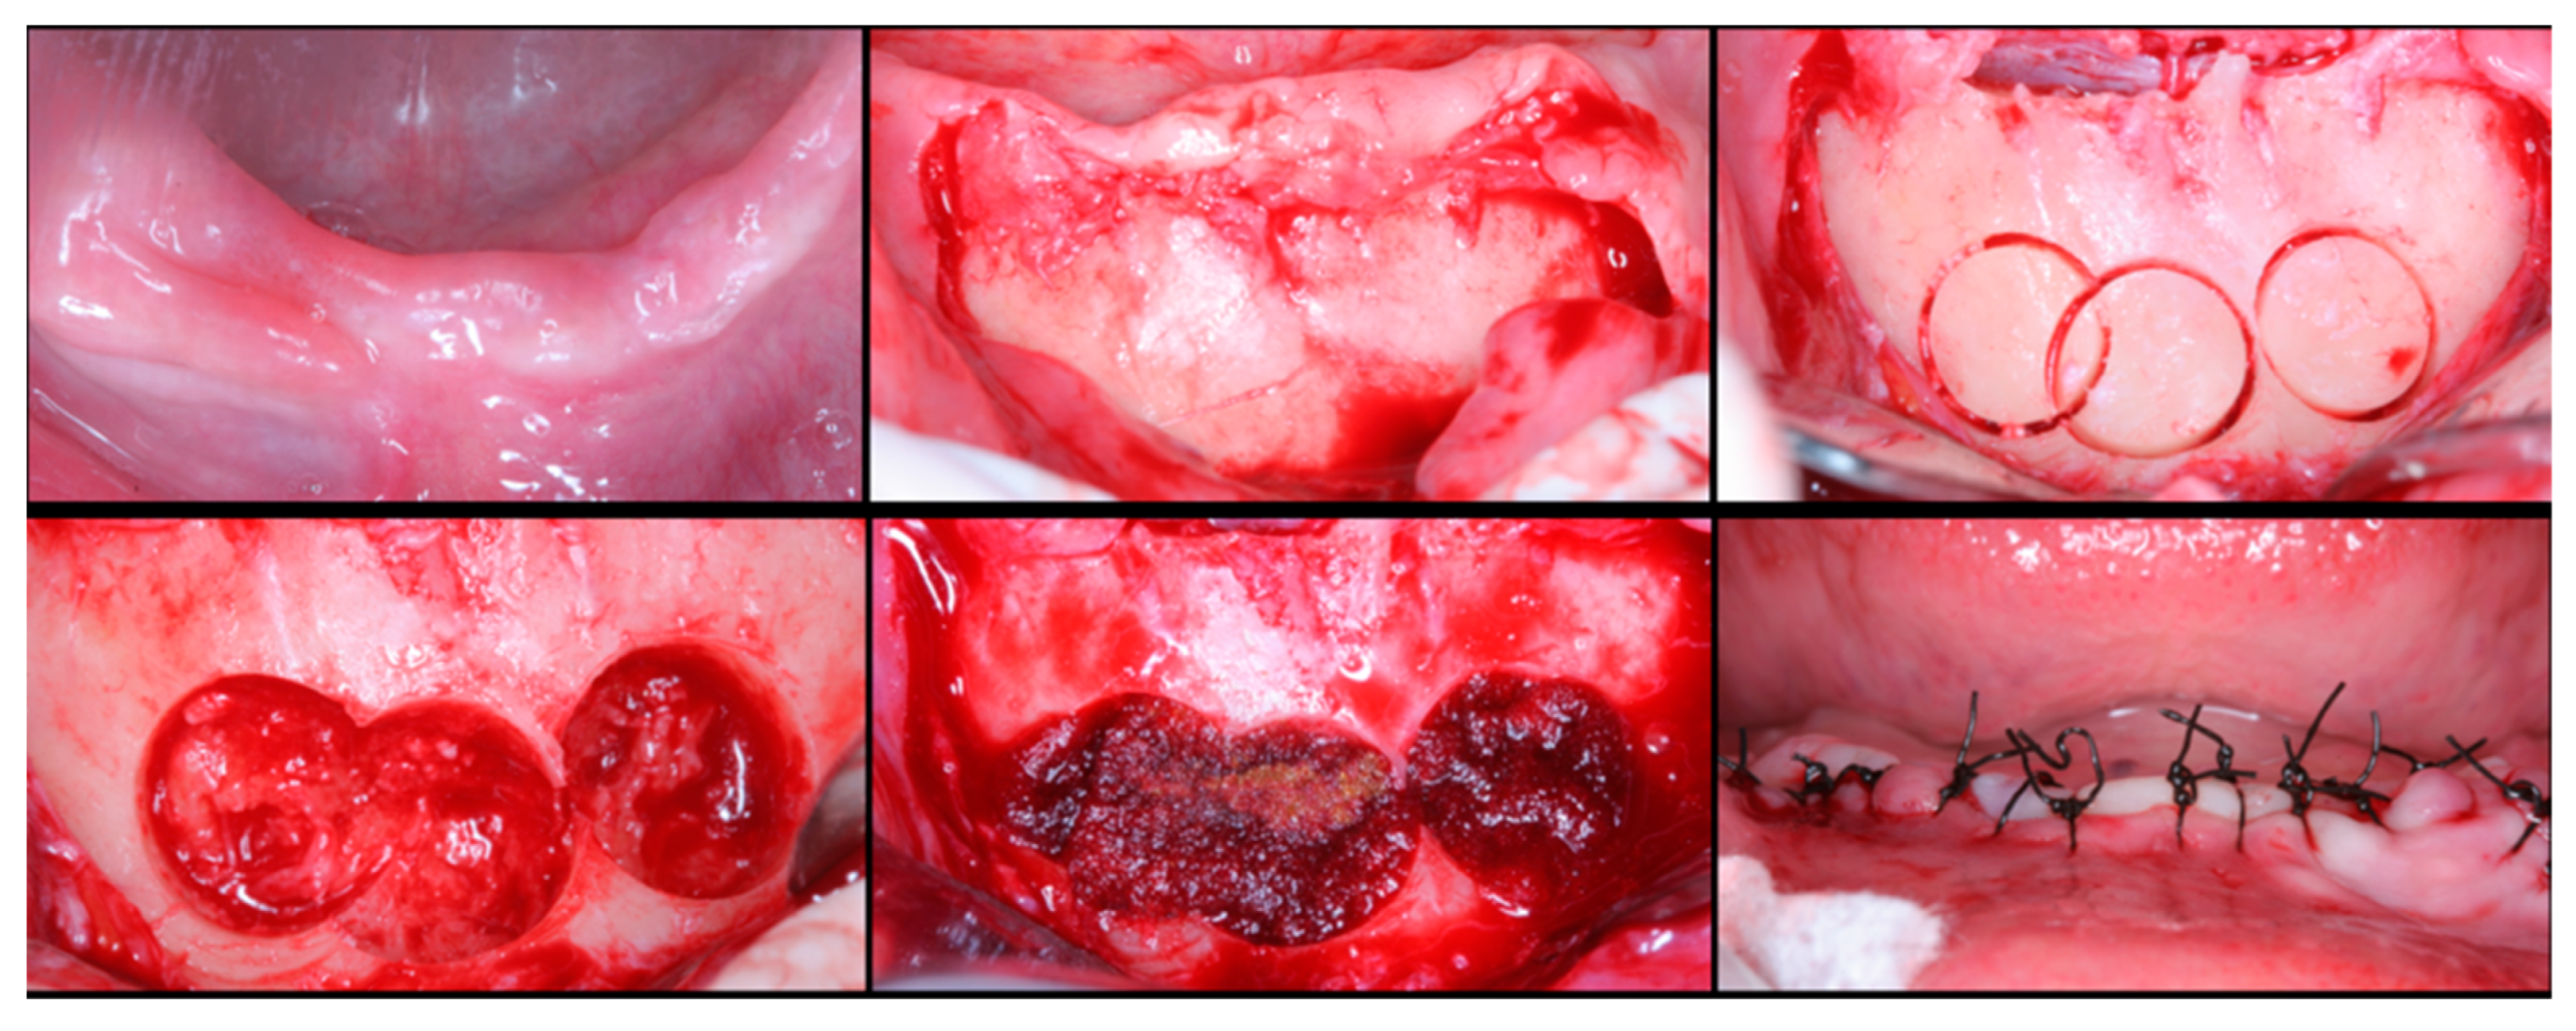

The surgical process, performed by the same surgeon, involved local anesthesia followed by incisions, flap detachment, osteotomy, and membrane elevation. Autologous bone from the mandibular branch (Figure 1) or the mental symphysis (Figure 2), or a porcine xenograft (Figure 3) were used as the graft materials for sinus augmentation. The protocol for this study involved using either two or three syringes of Oteobiol MP3, delivering a volume of approximately 2 to 3 cc per sinus. The contralateral sinus received a similar amount of autologous bone, either from the mental region (desmal with probably some bone of enchondral origin) or the mandibular ramus (desmal origin). Figure 3 and Figure 4 depict one example from each side of maxillary sinus augmentation treatment. Post surgery, the patients followed a prescribed protocol. After six months, a follow-up CT scan was conducted, and dental implants were placed. The final phase involved inserting healing abutments or prostheses, ensuring that no tooth–implant connections were established [20].

Figure 3. Step-by-step surgical demonstration of maxillary sinus elevation with xenograft. In the first row, left to right: incision in the fourth quadrant, flap detachment, and lateral osteotomy. In the second row, left to right: accessing the sinus, filling with xenograft, collagen membrane positioning, and sutures.